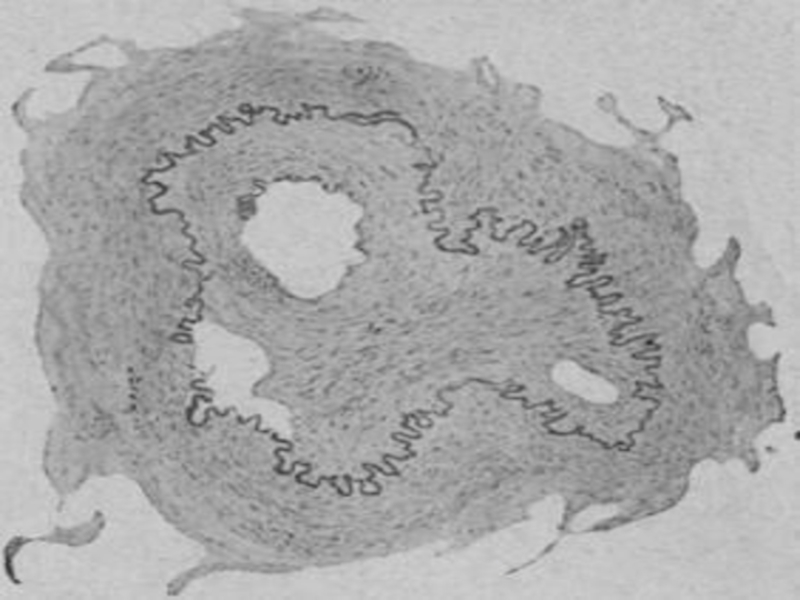

Слайд 21Поражение соудов

Поражаются сосуды разного калибра, но чаще других в патологический

процесс вовлекается аорта.

Развивается сифилитический мезаортит, часто приводящий к аневризме аорты.

Воспаление

может перейти на аортальный клапан и его заслонки. Они становятся белесоватыми, деформируются вследствие грубого рубцевания, характерного для сифилиса, срастаются между собой, что приводит к сифилитическому аортальному пороку.

Сифилис называют «королевством сосудов».